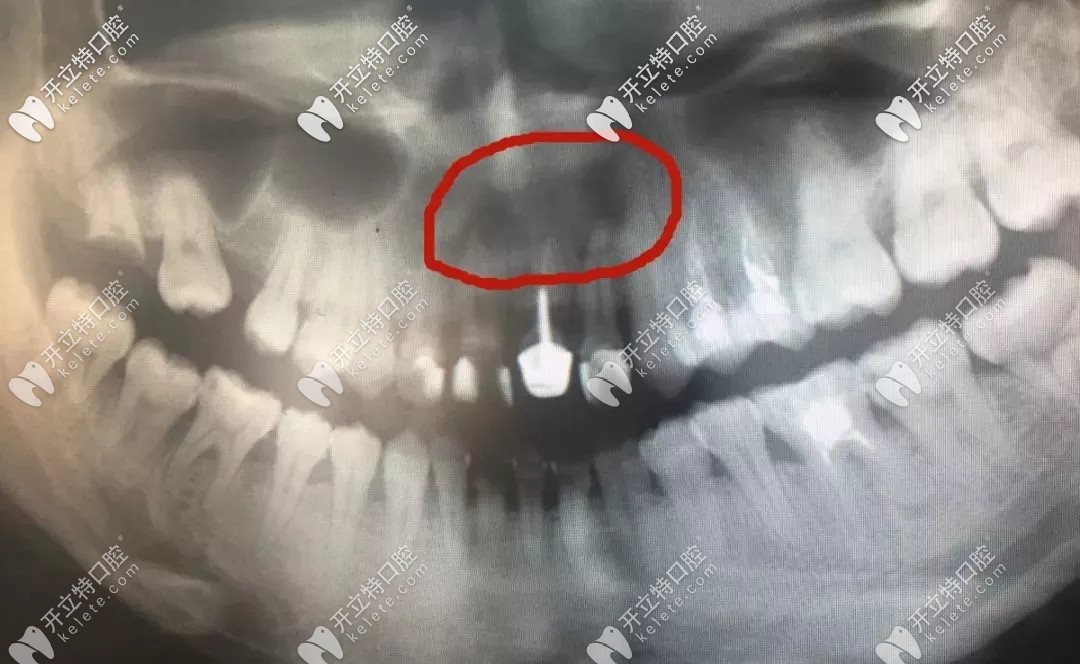

牙根尖的囊腫

▲牙根尖的囊腫

如果不及時摘除,會造成大面積上頜骨缺失,門牙的松動、脫落,以及鄰牙不保的后果。